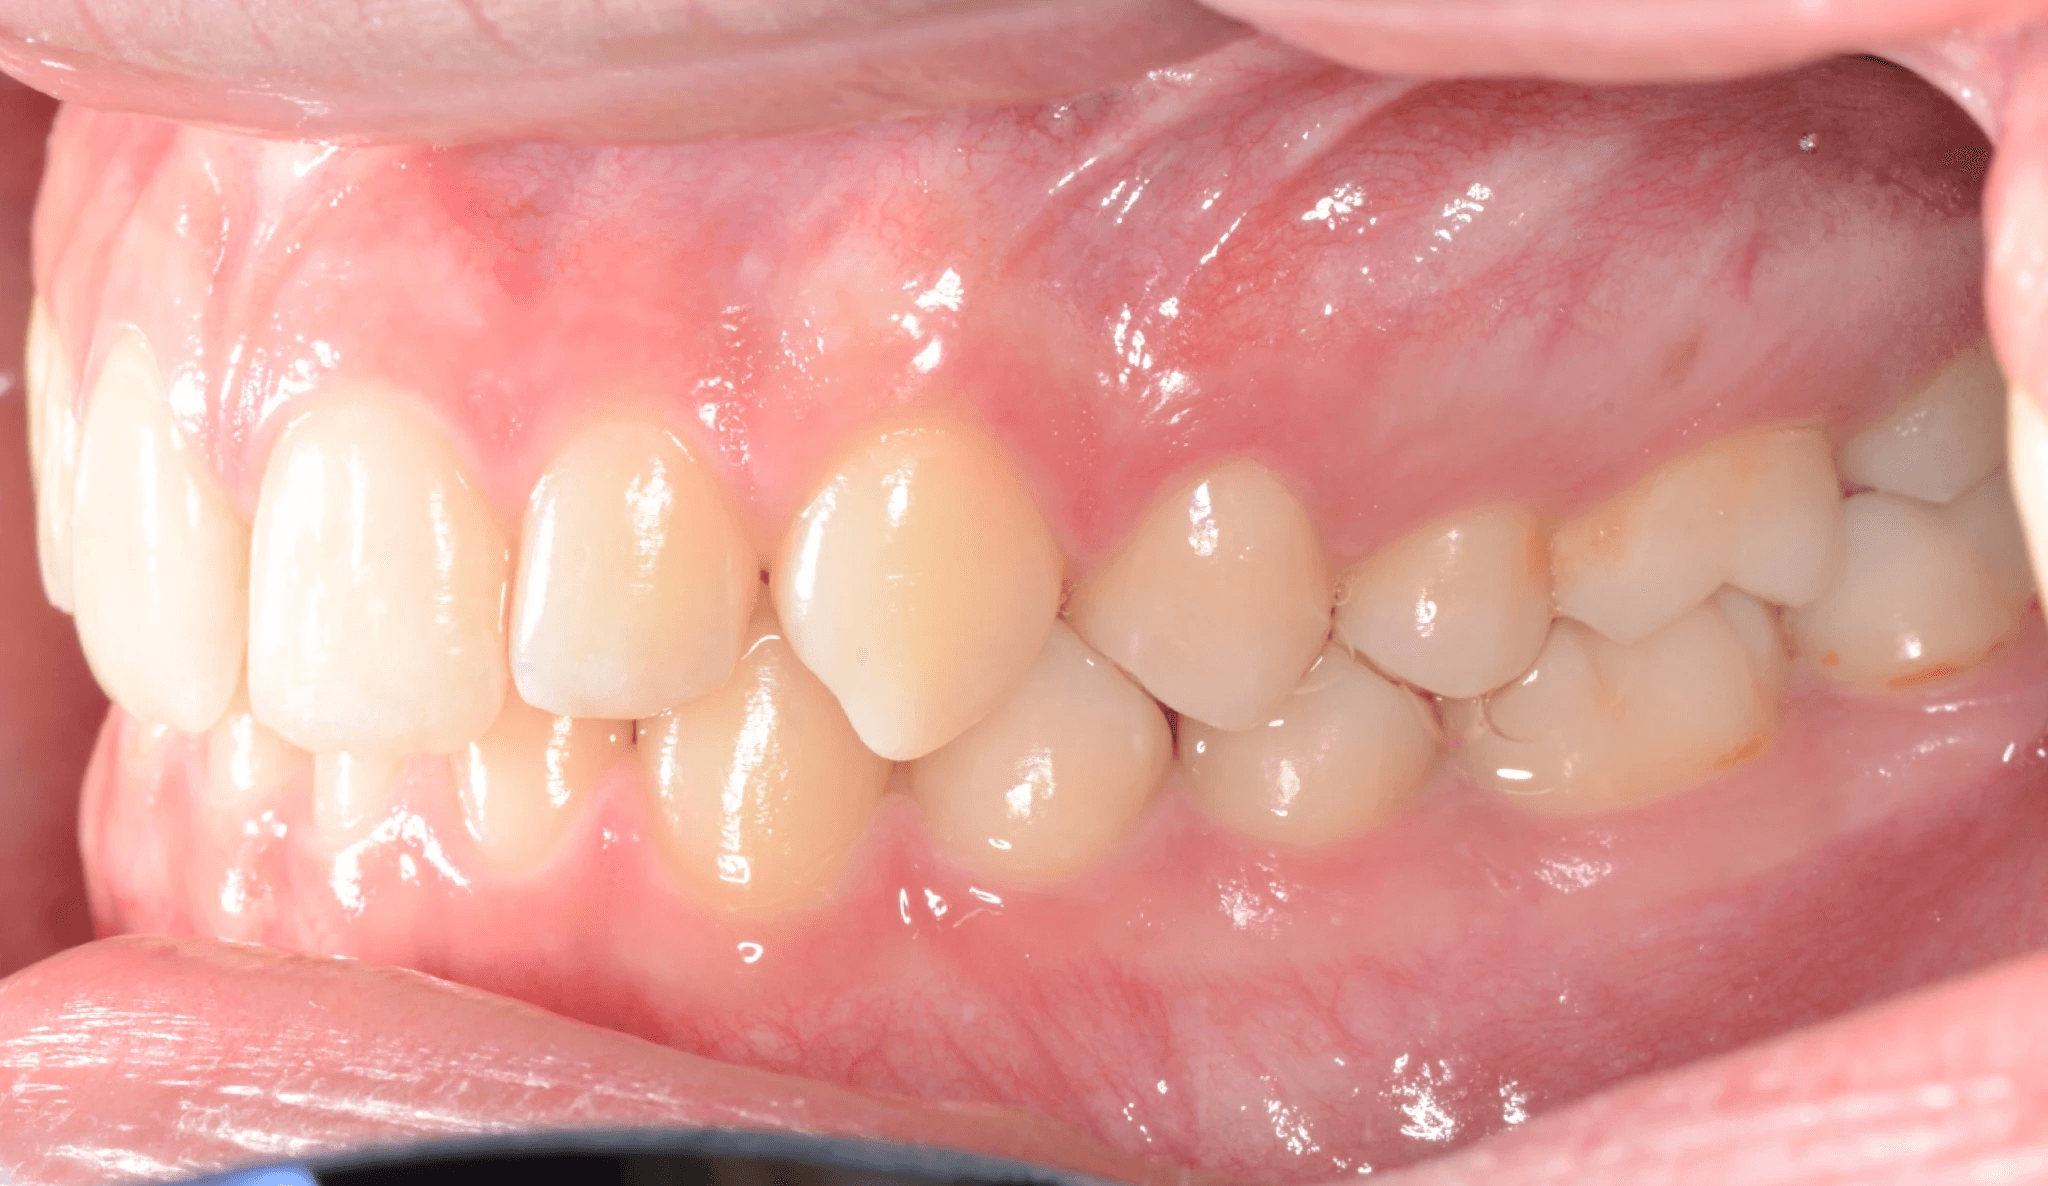

Initial treatment

INTRAORAL